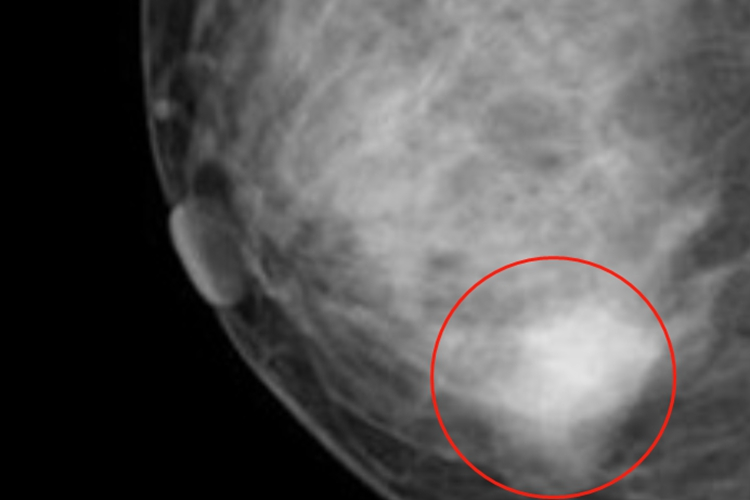

乳腺增生可表现为乳房疼痛、乳房肿块或者结节等,触摸局部质地较硬。乳房疼痛常为胀痛或刺痛,疼痛严重者不可触碰,甚至影响日常生活及工作,疼痛以乳房肿块处为主。乳房肿块发于单侧或双侧乳房内,单个或多个,形状有片块状、结节状等,乳房可有明显肿大的情况。影像学检查可有弥漫性密度增高,尤其是乳头下方,呈不均匀的片状影,边缘模糊。